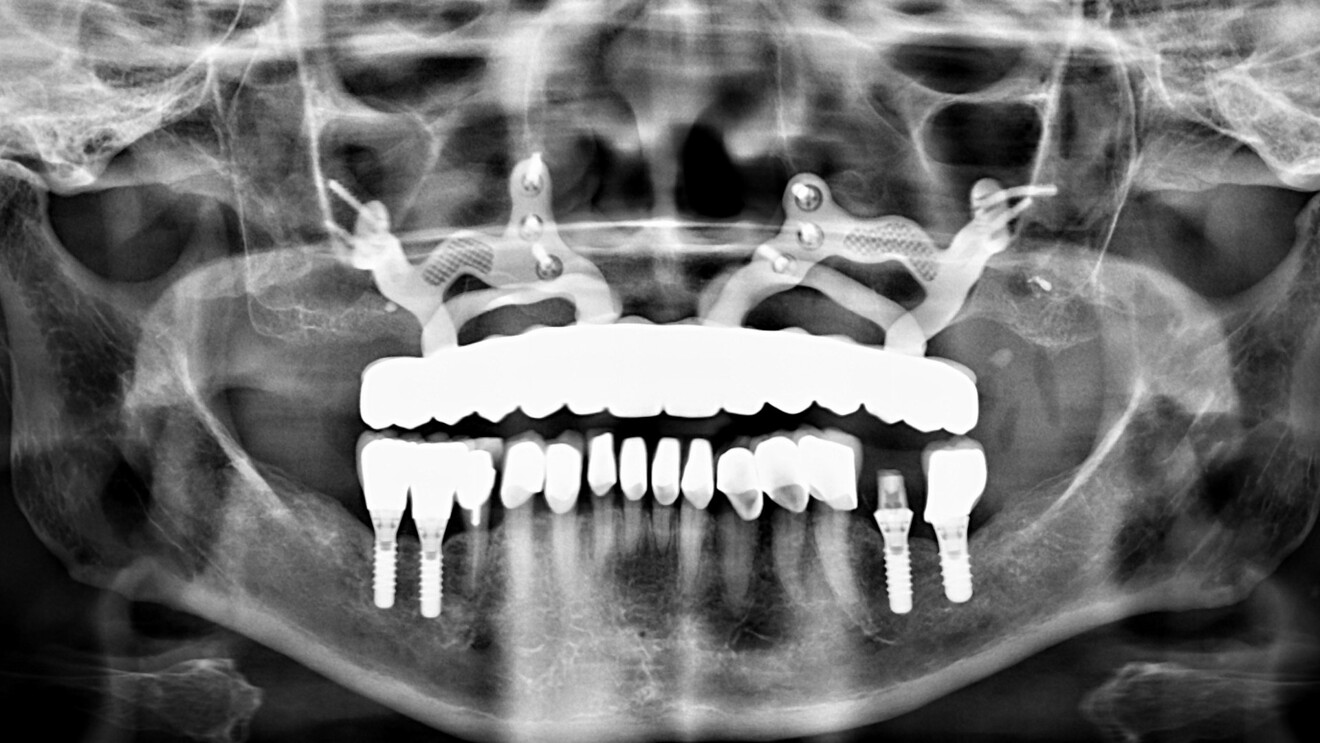

Fig. 2b : Courtoisie du Dr P Mestrallet. Orthopantomogramme postopératoire.